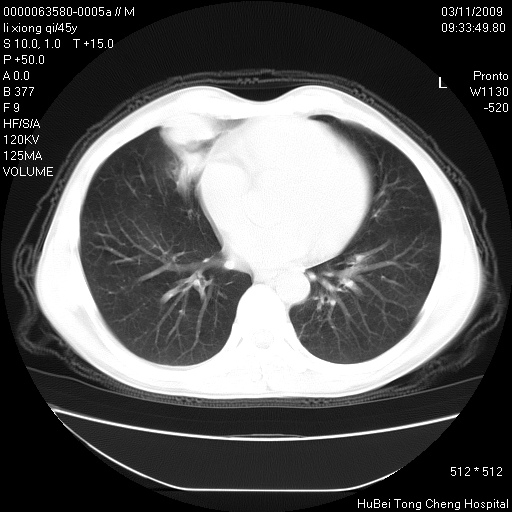

患者 男,45岁。胸痛,咳嗽伴痰中带血1月余。

临床诊断:肺结核?

胸部ct轴位平扫(层厚10mm,螺距1.5,重建间隔10mm),图像如下:

考虑肝癌肺转移